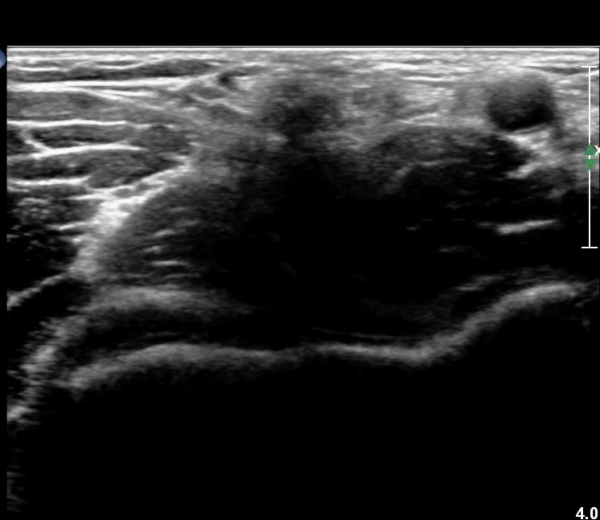

ÆÈ²ÞÄ¡ ¾ÕÂÊ ¿ÜÃø, ¼ÒµÎ(capitulum) Á¾´Ü¸é°Ë»ç¿¡¼­ ¼ÒµÎ Àü¸éºÎ¿Í ¿ä°ñµÎ Àü¸é¿¡ ¼ö¾×Àú·ù°¡ °üÂûµÊ(»çÁø 3, 4).